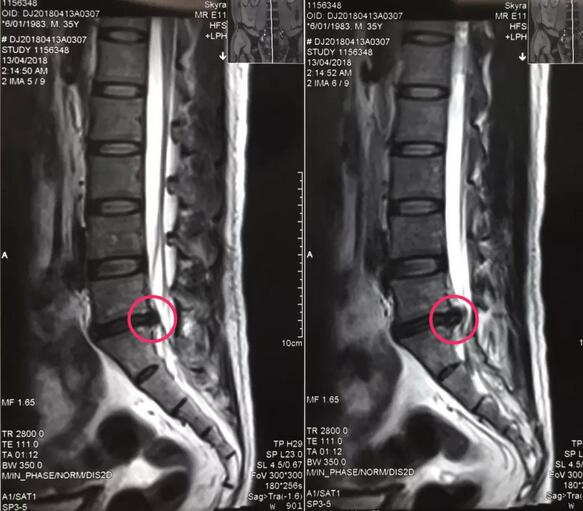

八零后李先生来自山西长治,是家里的顶梁柱,半年前开始出现腰痛不适,工作繁忙没有时间看病,后来突然加重并出现左下肢放射样抽痛,走路都走不了,在当地多家医院检查确诊为腰椎间盘突出症,治疗方案都是开刀手术,打钉固定,小李拒绝开放手术,回家卧床四个多月,仍然不能下地走路,亲朋友好友四处寻医问药,终于从病友群里打听到,六合彩生肖 可以微创手术,效果很好,就专程前来。骨一科专家团队给李先生进行了详细的查体和认真的读片,告诉李先生诊断确实是腰椎间盘突出症,适合孔镜微创,不用开放手术,不用打钉固定,李先生欣然接受。7月27日,骨一科微创团队为李先生实施了经皮椎间孔镜下髓核摘除术,手术一小时,术后下肢抽痛症状完全解除,终于可以下地走路了,李先生和家人对手术效果非常满意。